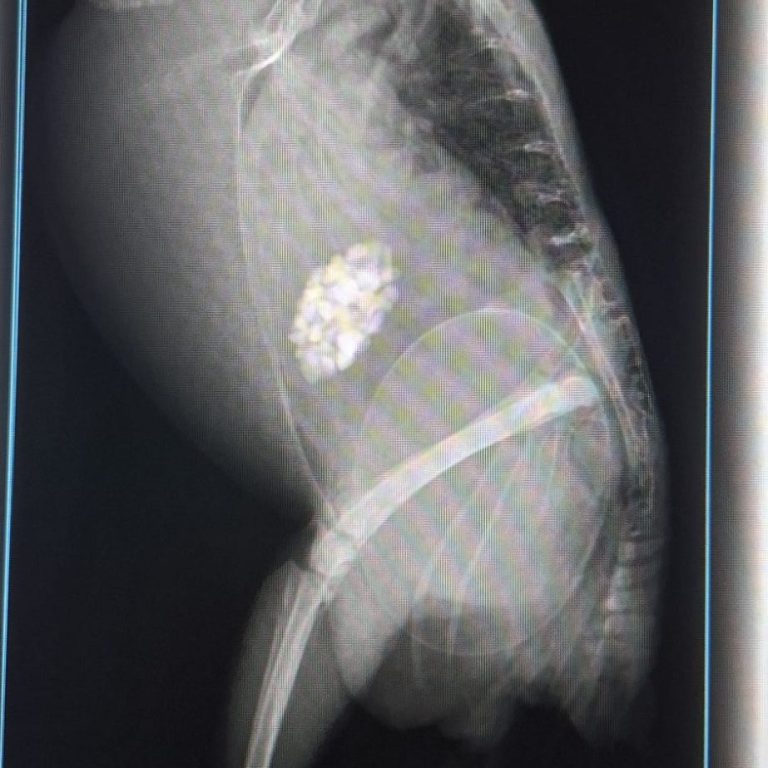

Vor Kurzem haben sich bei Nils erstmals Eier gebildet. Diese konnte sie jedoch aufgrund ihrer anatomischen Voraussetzungen nicht legen. Es kam zu einer akuten Legenot – einem lebensbedrohlichen Zustand. Ihr Zustand verschlechterte sich innerhalb kürzester Zeit dramatisch, sodass sie notfallmäßig unserer Tierärztin vorgestellt werden musste.

Das Ei musste operativ entfernt werden. Ein natürliches Ablegen wäre für Nils nicht möglich gewesen, da der Ausgang viel zu klein ist. Klar ist nun: Nils darf auf keinen Fall mehr Eier legen, da dies jedes Mal lebensbedrohlich für sie wäre.